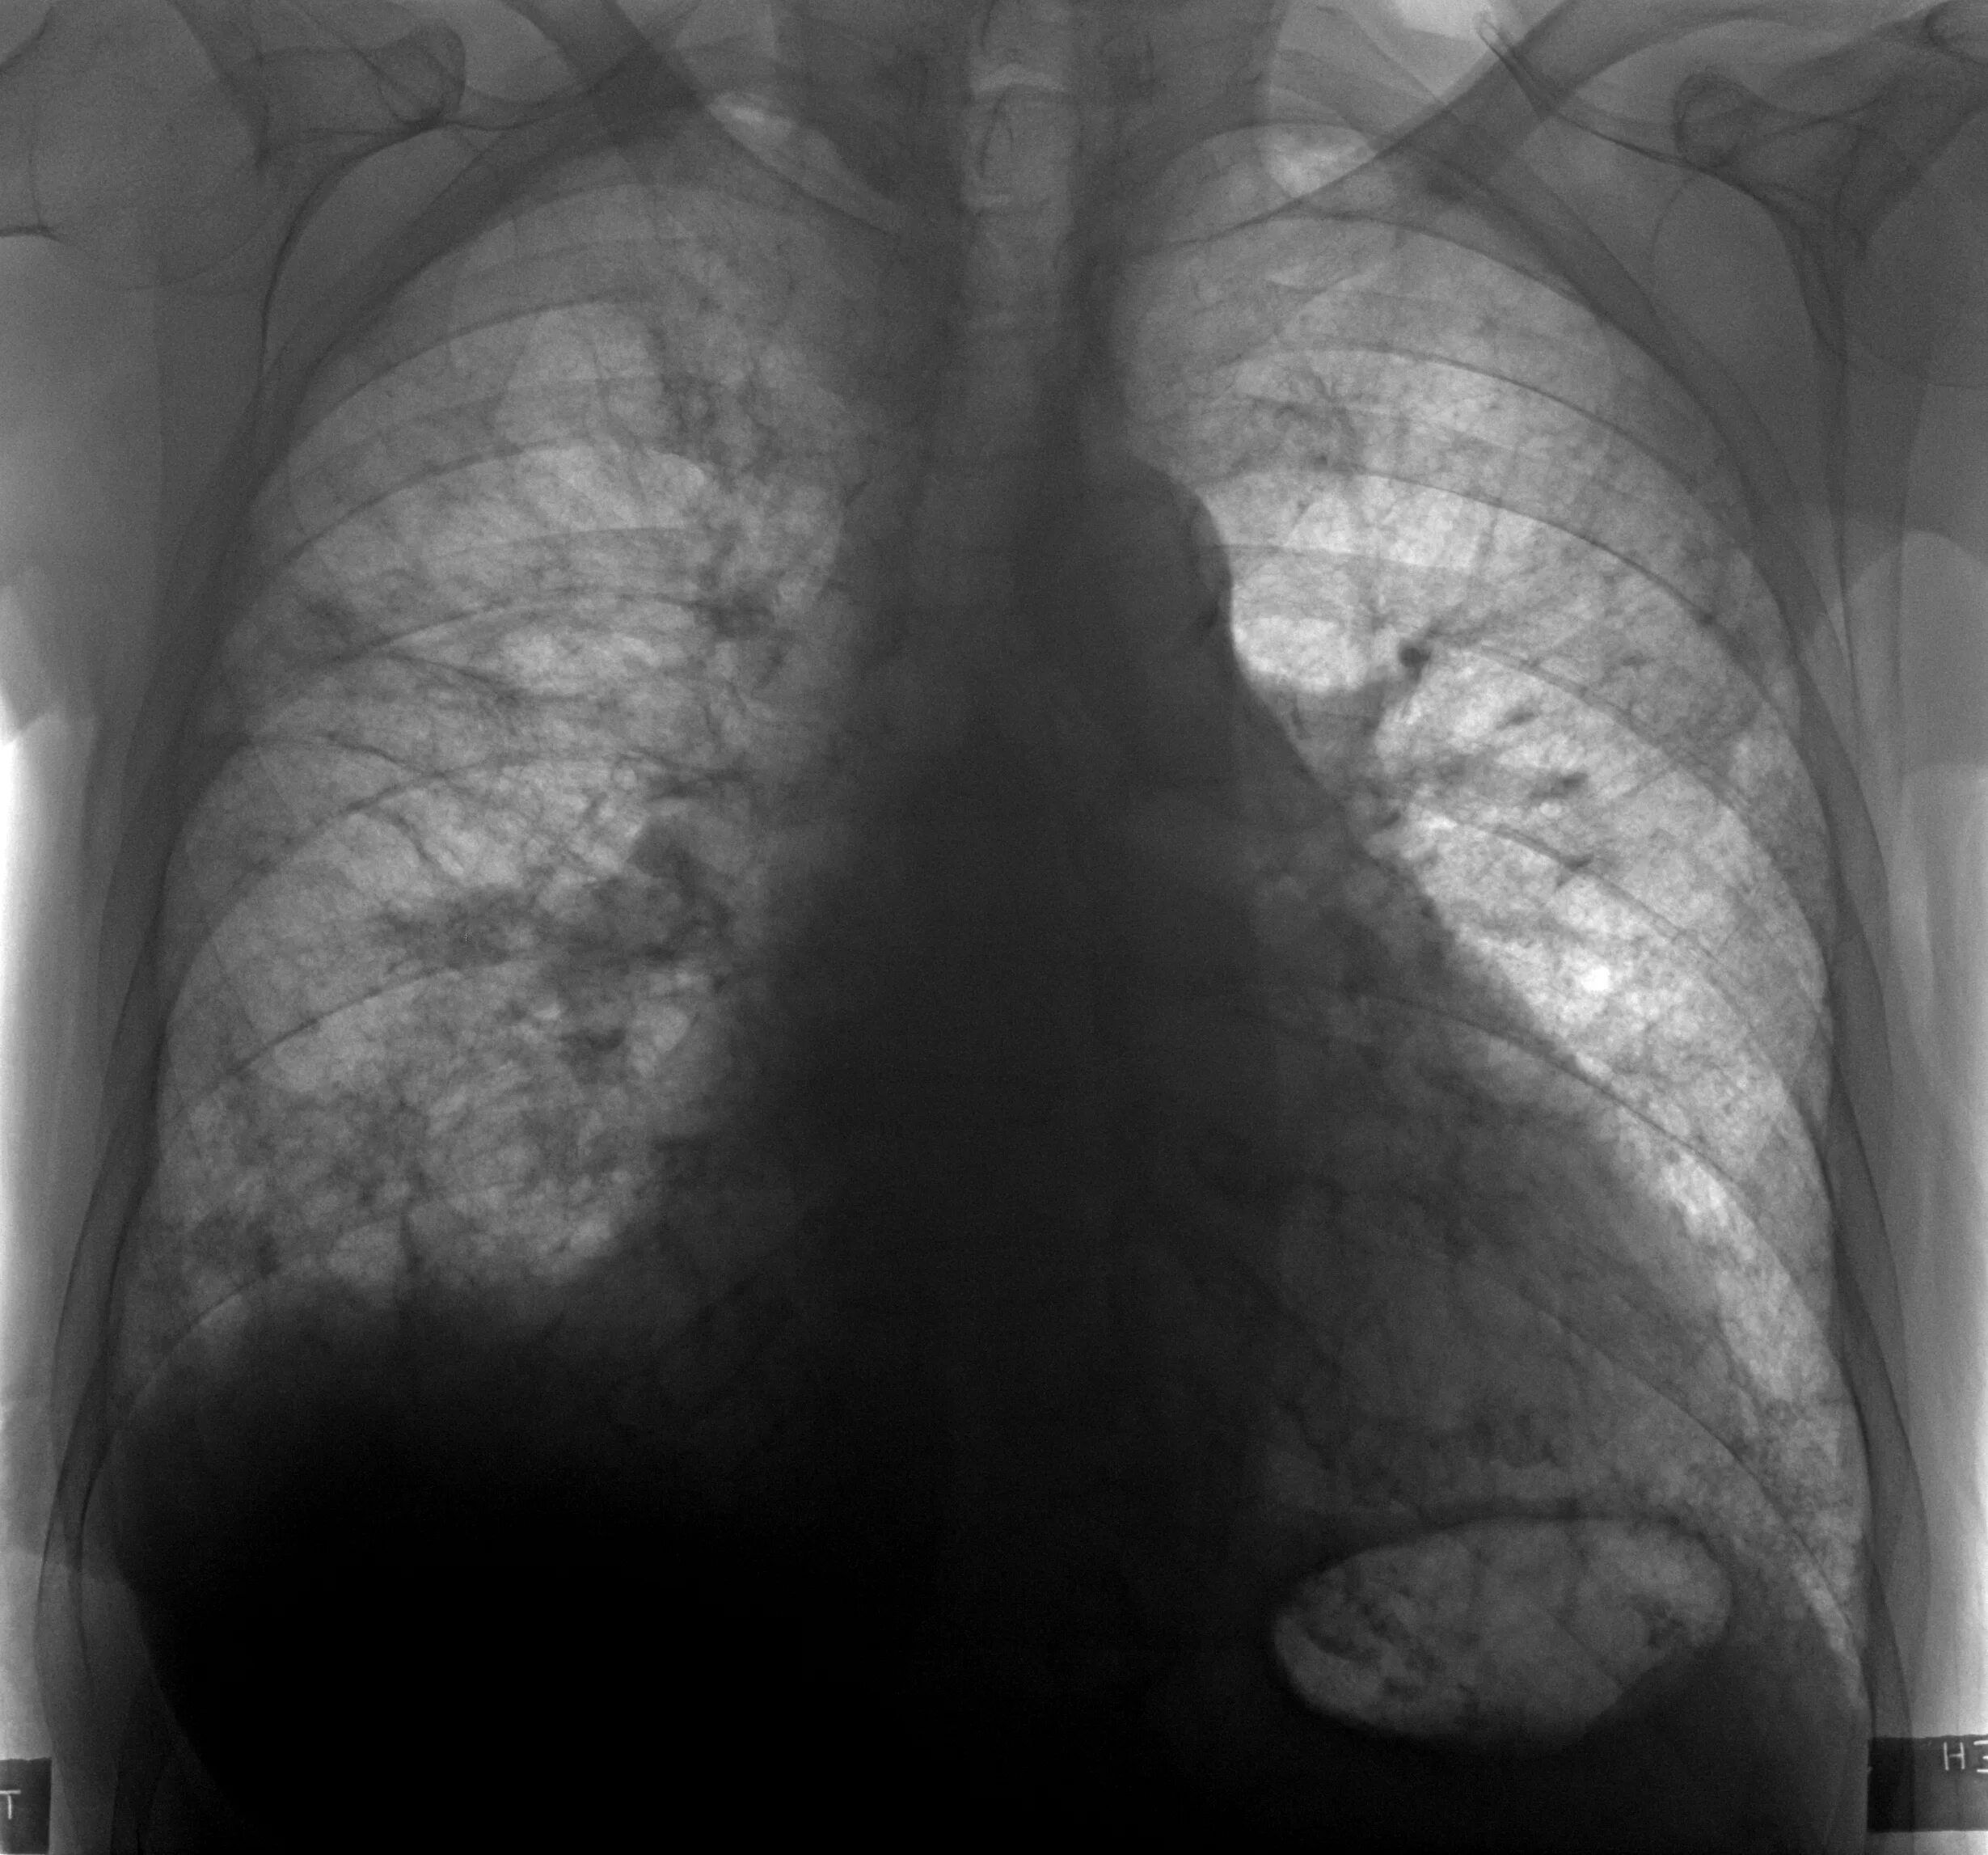

Пневмосклероз легких прогноз